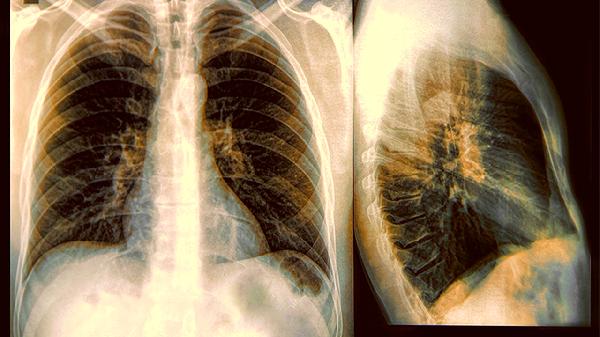

肺部CT能发现早期微小病变,建议高风险人群每年检查一次。早期发现的肺部问题,治愈.率会显著提高。